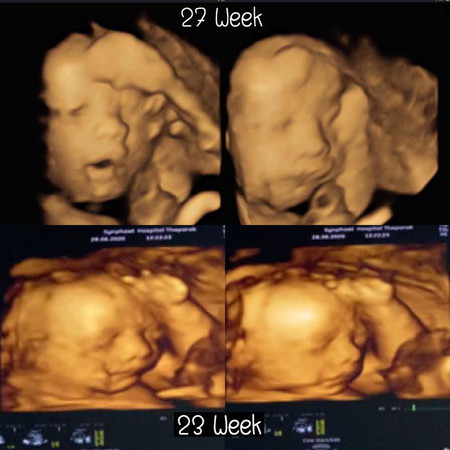

บ้านนี้ซาวด์4มิติ ตอน23+6week กับตอน27week แม่ๆว่าน้องหน้าเปลี่ยนมั้ยค่ะ บ้านอื่นซาวด์แล้วเป็นยังไงกันบ้างน่ารักขนาดไหนขอชมหน่อยค่ะ🥰🥰